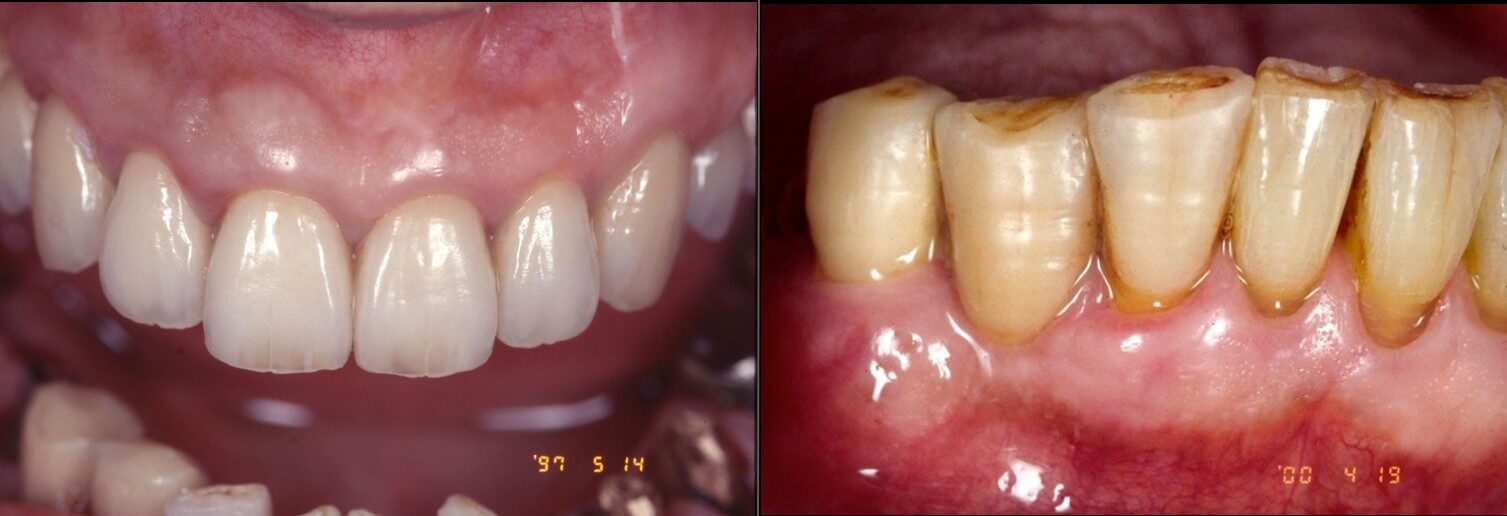

臨床例